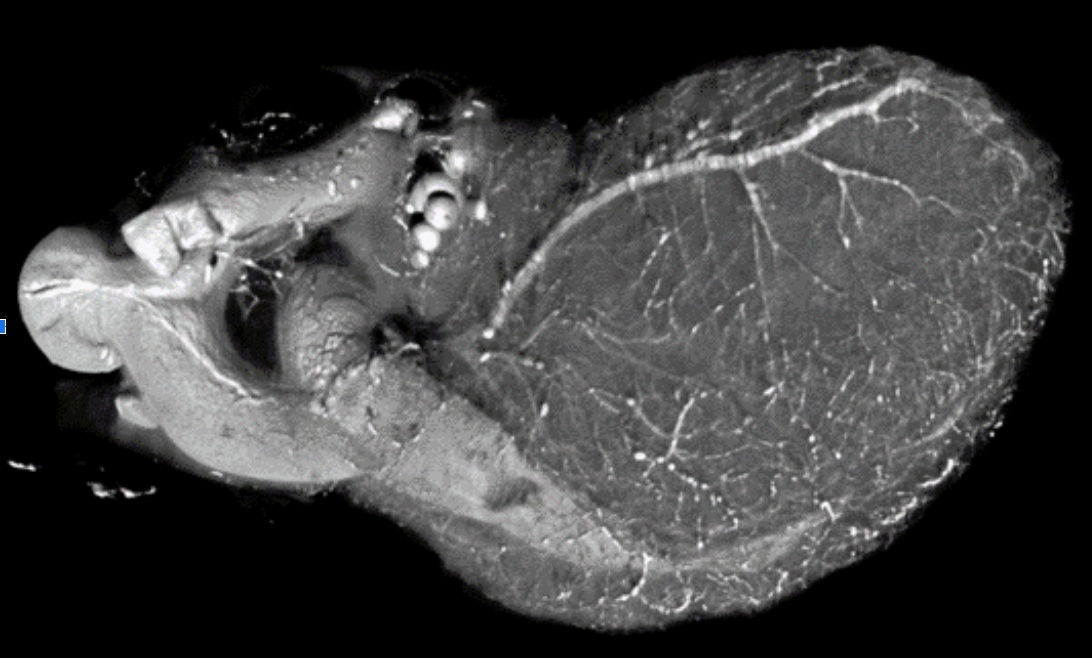

Vascular perfusions, heart

Vascular networks are complex, multi-dimensional, and challenging to image. SkyScan micro-CTs are an excellent imaging modality for vascular exploration, with high spatial resolution for studying the structure and organization of blood vessels.